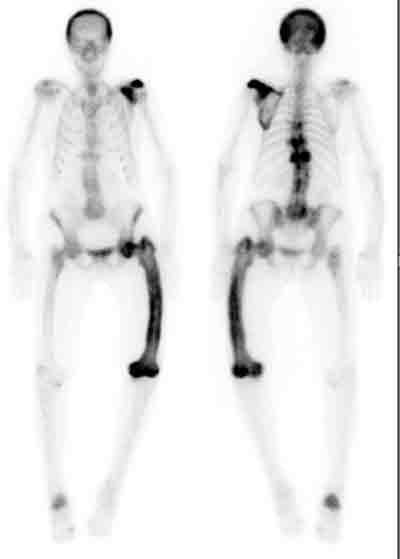

3 Isotope bone scanning in Paget’s disease

A patient with polyostotic Paget’s disease, showing involvement of the skull, left scapula, thoracic vertebrae (T7, T9 and T11), left femur and right calcaneum.